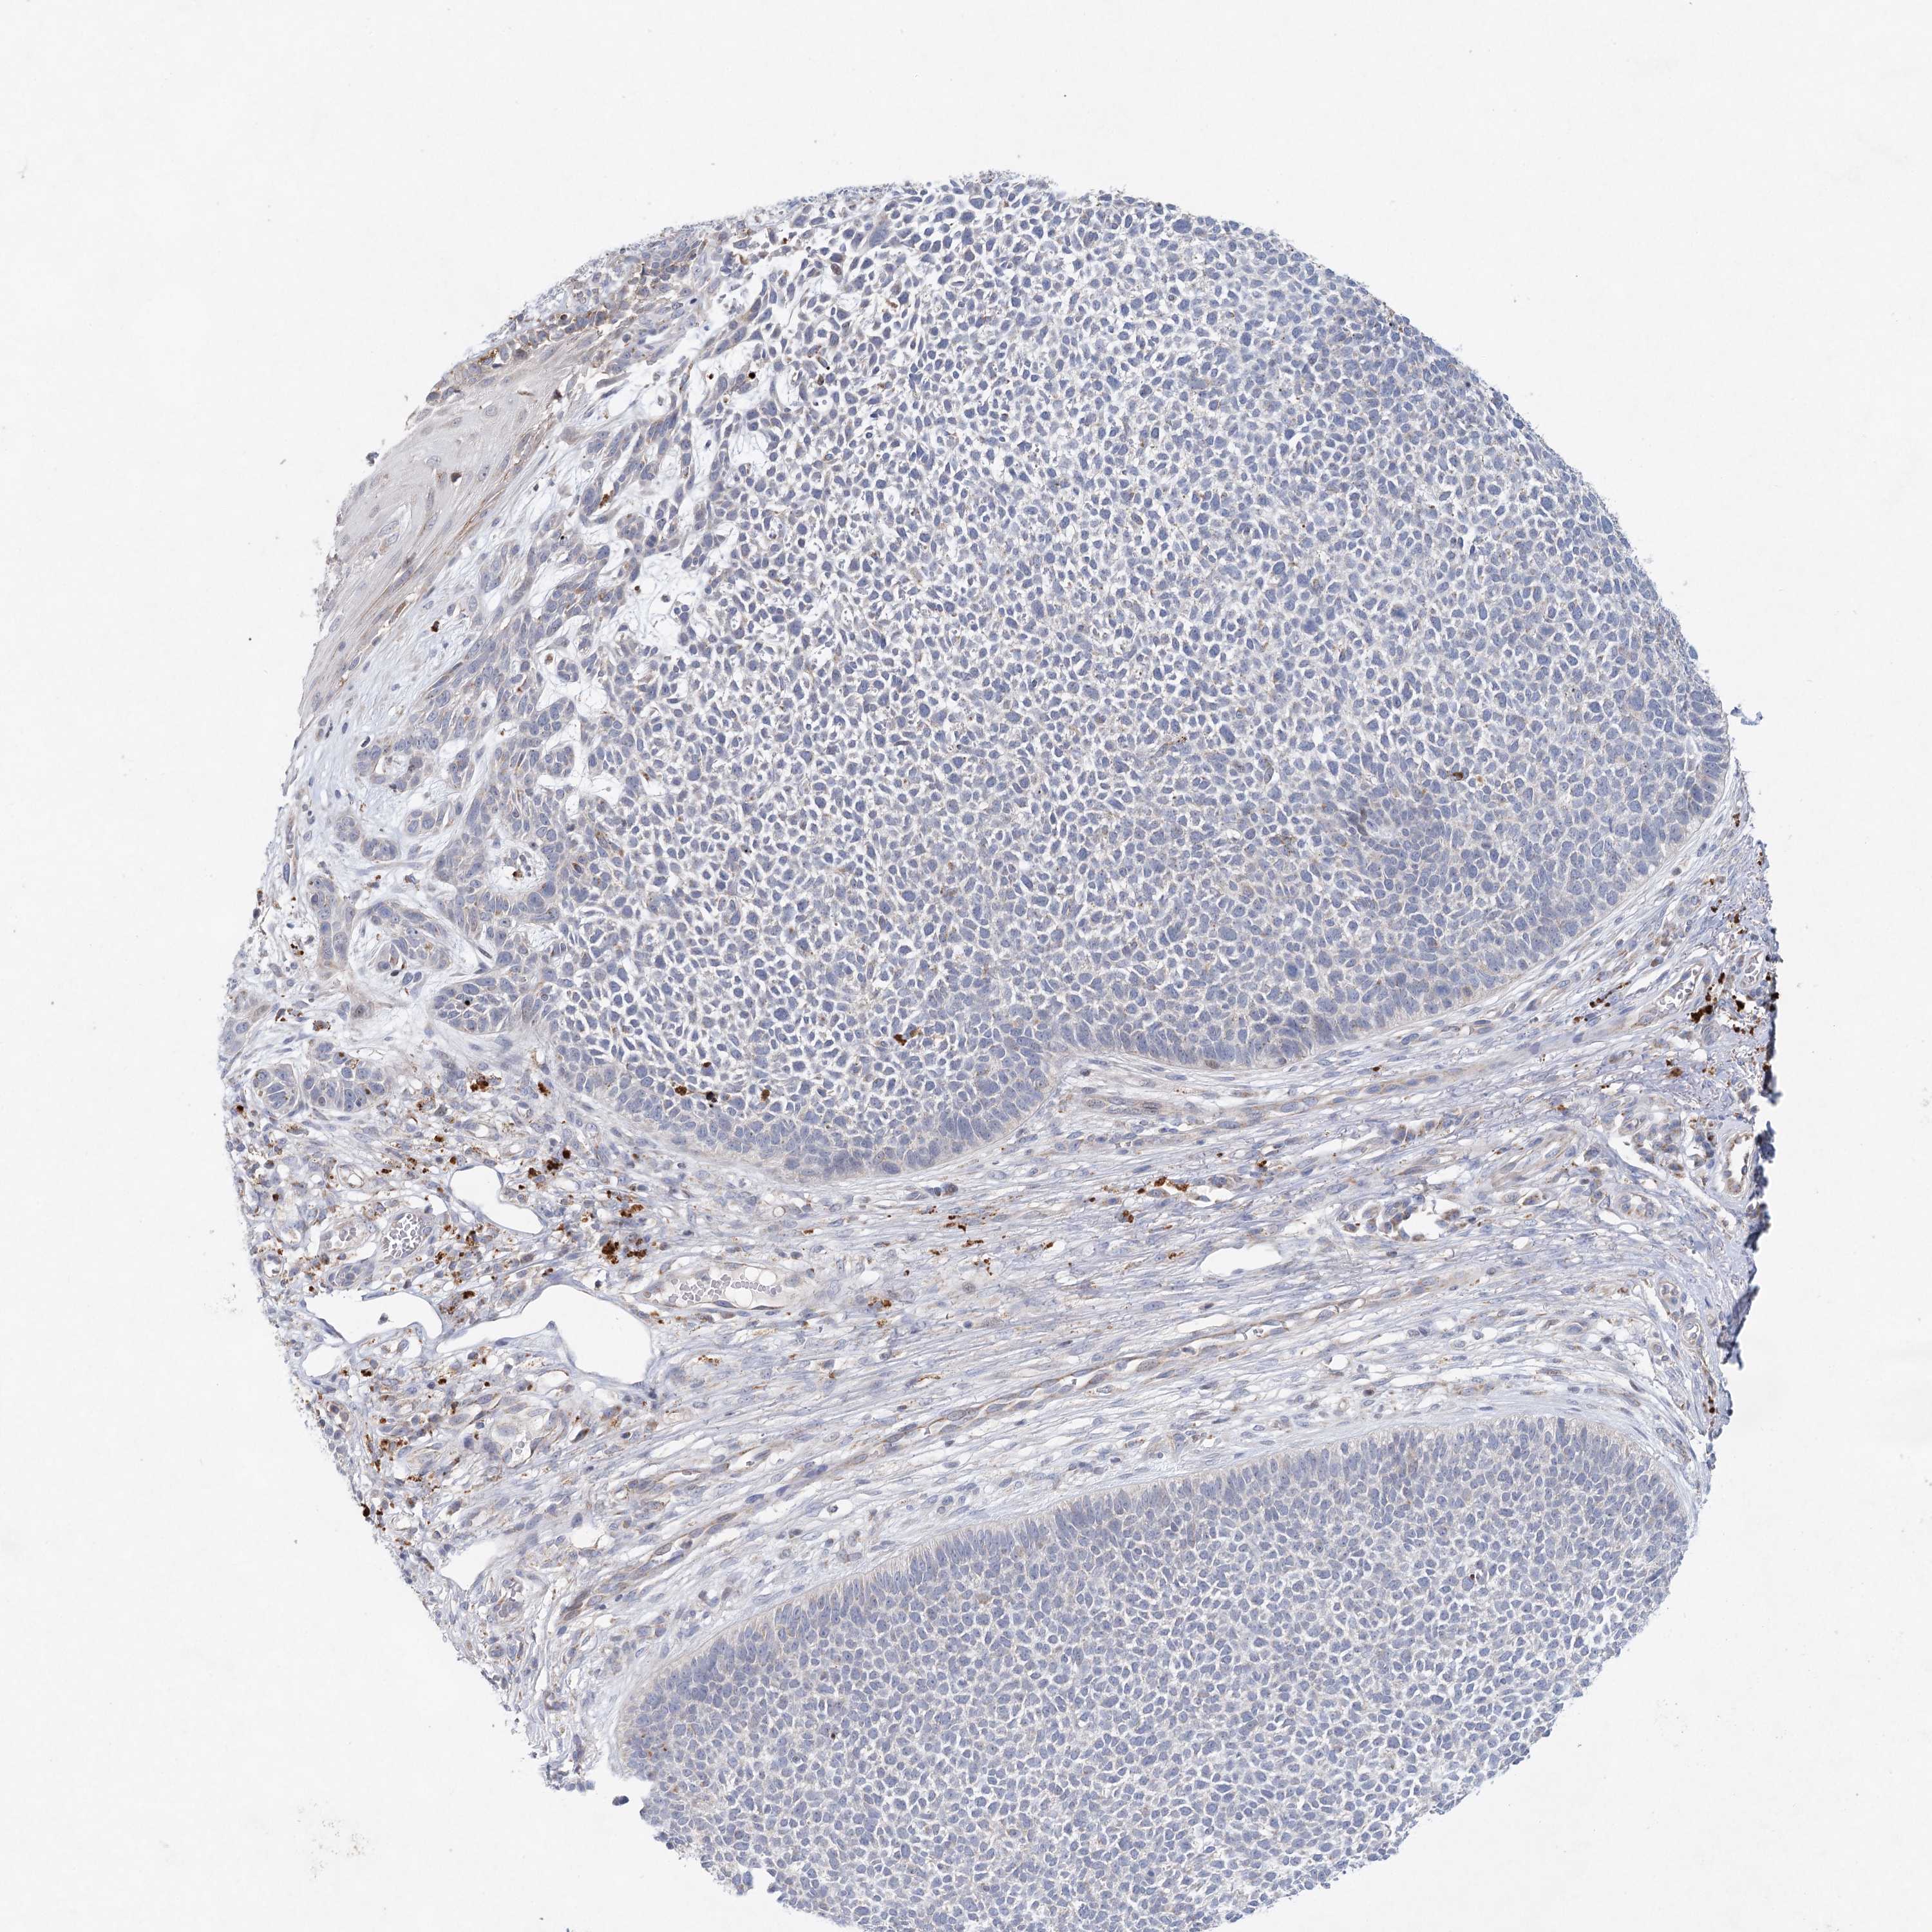

SKIN CANCER - Protein expressioni

A mouse-over function shows sample information and annotation data. Click on an image to view it in a full screen mode. Samples can be filtered based on level of antibody staining by selecting one or several of the following categories: high, medium, low and not detected. The assay and annotation is described here.

Antibody stainingi

Antibody staining in the annotated cell types in the current human tissue is reported as not detected, low, medium, or high, based on conventional immunohistochemistry profiling in selected tissues. This score is based on the combination of the staining intensity and fraction of stained cells.

Each image is clickable and will lead to virtual microscopy that enables deeper exploration of all samples and also displays staining intensity scores, fraction scores and subcellular localization as well as patient and tissue information for each sample.

Antibody HPA038246

Staining

High

Medium

Low

Not detected

Intensity

Strong

Moderate

Weak

Negative

Quantity

>75%

75%-25%

<25%

None

Location

Nuclear

Cytoplasmic/membranous

Cytoplasmic/membranous,nuclear

Basal cell carcinoma